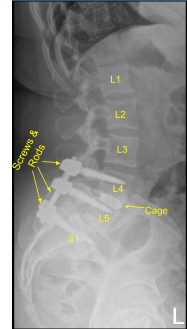

Next, a new CT scan was obtained, which showed correct positioning of the new pedicle screws and interbody spacer. Bilateral transverse processes of L4, L5, and lateral ala were decorticated for arthrodesis. Pre-cut, pre-contoured rods reflected and placed across the tulips from L4 to S1 and secured with locking caps and finally tightened with the torque and anti-torque device.

Morselized autograft and allograft were placed into lateral gutters from L4 to S1 for the arthrodesis. Wound was irrigated copiously throughout the procedure. Vancomycin powder was applied. Closure was performed by a plastic surgeon.